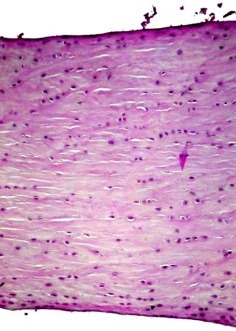

17

Q

A

Condylar head of adult